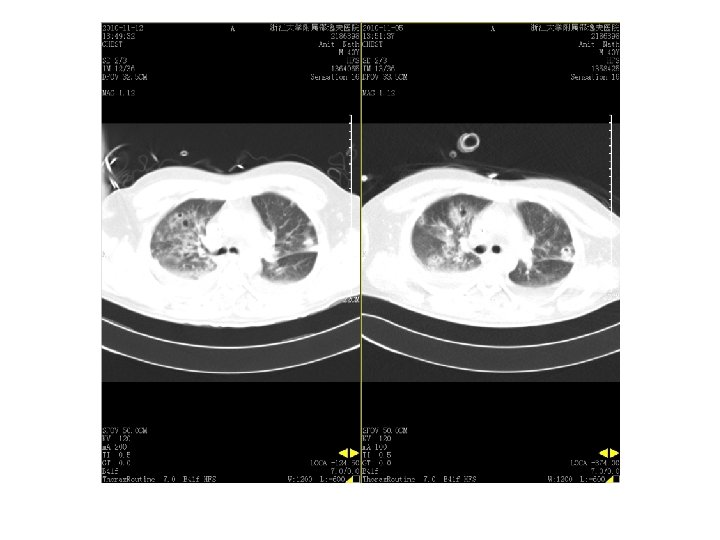

11. 12 vs 11. 5

2010. 9. 13复查CT